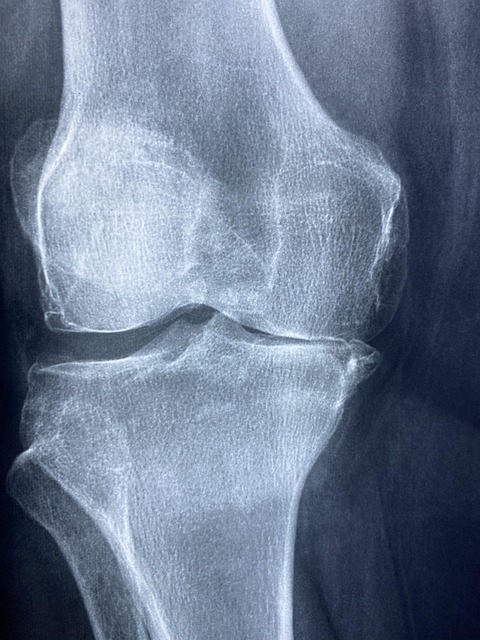

관절염은 가장 흔한 관절 질환으로, 골관절염(퇴행성 관절염)과 류마티스 관절염이 대표적입니다. 골관절염은 관절 연골의 마모로 인해 발생하며, 주로 체중을 지지하는 관절(무릎, 엉덩이)에 영향을 미칩니다. 류마티스 관절염은 자가면역 질환으로, 면역 체계가 관절 내막을 공격하여 염증과 통증을 유발합니다.

먼저 무릎 관절을 위한 운동부터 살펴보겠습니다. 무릎은 체중을 지지하는 주요 관절로, 골관절염이 흔히 발생하는 부위입니다. 무릎 관절 강화를 위한 첫 번째 운동은 '앉았다 일어서기'입니다. 의자에 앉은 상태에서 발을 어깨 너비로 벌리고, 팔을 앞으로 뻗거나 의자 팔걸이를 사용하여 천천히 일어섭니다. 그 후 천천히 다시 앉는 동작을 10-15회 반복합니다. 이 운동은 대퇴사두근과 햄스트링을 강화하여 무릎 안정성을 향상시킵니다.